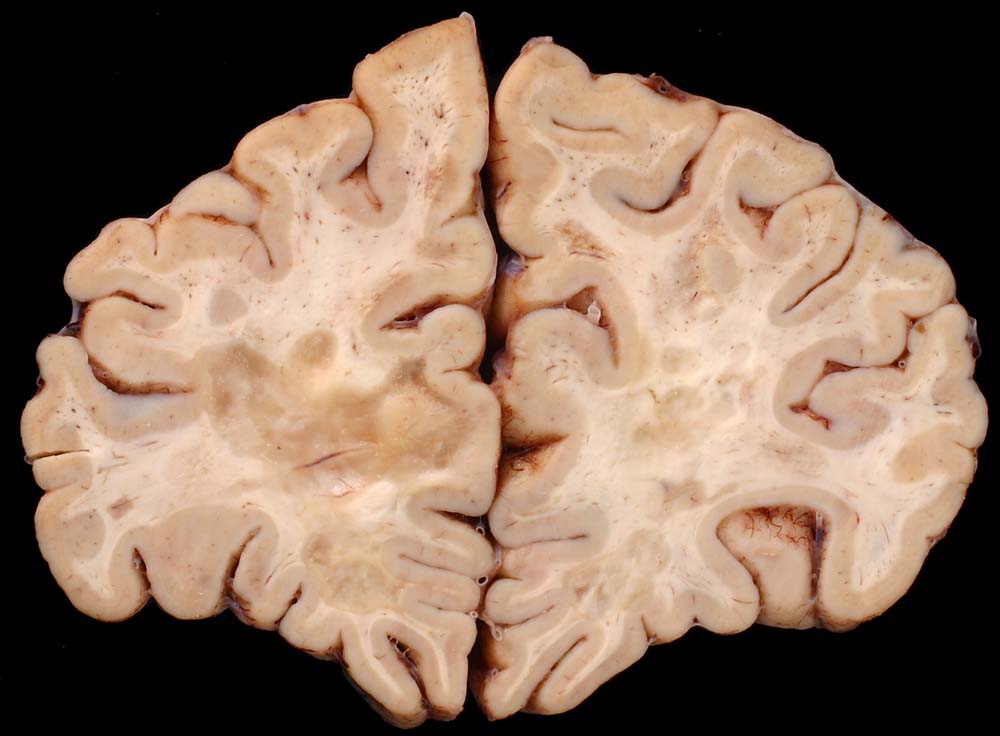

An Frontalschnitten durch das Gehirn fallen makroskopisch Entmarkungsherde vor allem im unmittelbar periventrikulären Marklager auf (um die Vorderhörner, die Cella media und um die Hinterhörner). Nicht selten finden sie sich auch um den Aquädukt und am Boden des 4. Ventrikels. Die Farbe der Herde hängt vom Alter des Prozesses ab (eher rosa bei frischen, eher grau bei alten Herden), die Konsistenz ist weich bei frischen, zunehmend derb bei alten Herden durch Gliafaservermehrung. Histologisch zeigen frische Entmarkungsherde in den ersten Tagen eine Oligodendrogliavermehrung. Ihr folgt mit beginnendem Markabbau eine Mikrogliareaktion. Mikrogliazellen, Monozyten und Makrophagen phagozytieren die Markscheidenzerfallsprodukte (> 10160) (> 10159), die teilweise lichtmikroskopisch im Zytoplasma erkennbar sind (> 10161). Lymphozyten und Plasmazellen sind vor allem perivenös an den Herdrändern lokalisiert. Zusätzlich proliferieren faserbildende Astrozyten (> 10162). In älteren Herden (vorliegendes Präparat) fehlen die Markscheiden praktisch vollständig. Axone bleiben erhalten und es besteht eine dichte Fasergliose. Diese ausgebrannten Herde überwiegen beim chronisch Erkrankten. Auch bei ihm können allenfalls noch frischere Stadien gefunden werden.

Makroskopie

Befund

Pathologischer Befund

Normalbefund